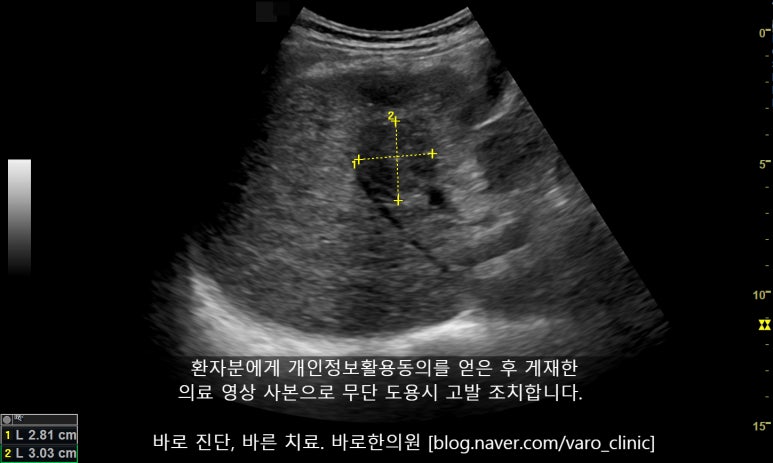

원발성 간암으로 감마지티피가 높아졌던 환자분의 초음파영상

혈액 중에 감마지티피는 대부분 간, 담에서 유래하여 [간, 담질환의 중요한 진단 지표]가 됩니다. 간염, 간경변, 간암 등 대부분의 간 질환에서 GGT는 상승하는데, 특히 담관 폐쇄성 질환에서 가장 높아져 정상치의 10배 이상 치솟아 올라갑니다.

돌처럼 딱딱한 결석이나 주변 조직으로 파고 드는 암(악성 종양) 덩어리가 담관을 눌러 막아버리면 급격하게 높아지는 것이죠.